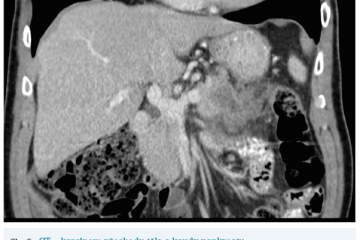

Několik studií se zabývalo AI asistovanou CT detekcí karcinomu pankreatu s AUC 0,79–0,99 %,6–8 tedy přesností porovnatelnou s přesností práce zkušeného radiologa. Stran časné detekce proběhla studie posuzující přesnost AI modelu v detekci karcinomu pankreatu v období 3–36 měsíců před prvními projevy onemocnění. Zařazeno bylo 155 pacientů s karcinomem pankreatu a 265 zdravých kontrol. AI model zde dosáhl AUC 0,98, což výrazně předčilo radiology, kteří při popisování stejných případů dosáhli AUC 0,66.9 Studie využívající DL model pro rozlišení zdravé slinivky od nálezu pankreatických neoplazií, tedy karcinomu pankreatu, intraduktální papilární mucinózní neoplazie (IPMN), serózních a mucinózních cystických neoplazií a solidní pseudopapilární neoplazie, byla prezentována s AUC 0,91, tedy opět odpovídající přesnosti popisu radiologa.10 Pro další vývoj a možné klinické využití bude potřeba přístupu k rozsáhlému archivu CT snímků karcinomu pankreatu, aby se ML modely mohly zdokonalovat. Další studie se věnovaly AI asistované diferenciální diagnostice. Ta bývá u lézí pankreatu velmi obtížná a pokrok v této problematice je tak velmi přínosný. Mezi nejzajímavější patří studie zabývající se rozlišením serózních a mucinózních cystadenomů s AUC 0,932.11 Další studie zkoumala úspěšnost rozlišení karcinomu pankreatu od zbytnění pankreatu při určitých formách chronické pankreatitidy (MFP – mass forming pancreatitis) s AUC 0,866.12 V další studii byla AI využita k rozlišení fokální autoimunitní pankreatitidy od karcinomu pankreatu s AUC 0,97.13 V rámci MR proběhlo několik studií, které se zaměřily na AI asistované zachycení a klasifikaci pankreatického karcinomu či IPMN. Studie klasifikující IPMN pomocí konvoluční neuronové sítě (CNN – convolutional neural network) byla schopna rozlišit dysplazii vysokého stupně od přítomnosti karcinomu se senzitivitou 76 %, specificitou 78 % a AUC 0,78.14 Další studie porovnávala AI modely CT a MR v predikci maligního IPMN. Výsledky ukázaly, že MR model s AUC 0,94 byl přesnější než CT model s AUC 0,864.15 S využitím PET/CT byl prozkoumán AI model rozlišující od sebe akutní pankreatitidu a karcinom pankreatu s AUC 0,9668.16 Výsledky AI v oblastech zobrazovacích metod jsou tak slibné. Dosahují minimálně přesnosti srovnatelné s radiologem a zejména v problematice časných karcinomů pankreatu člověka svojí přesností převyšují (obr. 1–5).